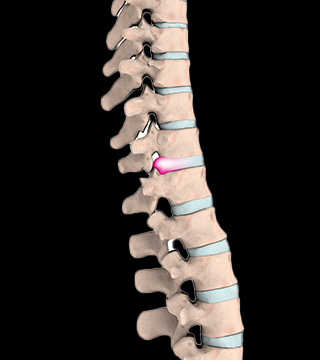

디스크가 밀려나와 척추 신경을 압박하여 통증을 일으키는 질환으로, 허리에 흔히 발생하고 요통과 함께 다리가 아픈 증상이 있으며, 목디스크의 경우도 통증과 함께 팔의 힘이 약해지거나 감각이상, 마비증상이 나타납니다.

노화나 외부적인 자극으로 인해 디스크가 손상을 입으면서 섬유륜이 손상 혹은 파열되면서 디스크 내부의 수핵이 빠져 나와 지나가는 신경을 압박해 증상이 나타나는 질환입니다.